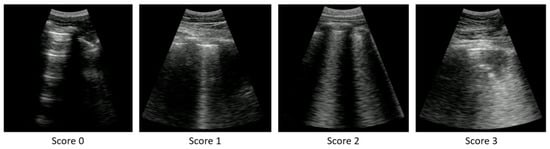

| Score | Finding | Fleiss Kappa (k and 95% CI) | Agreement | |

|---|---|---|---|---|

| 0 | Normal/A-lines | 0.74 | [0.71–0.76] | Substantial |

| 1 | Individual B-lines | 0.36 | [0.33–0.39] | Fair |

| 2 | Confluent B-lines < 50% | 0.26 | [0.24–0.29] | Fair |

| 3 | Confluent B-lines > 50% & Consolidations | 0.50 | [0.47–0.53] | Moderate |